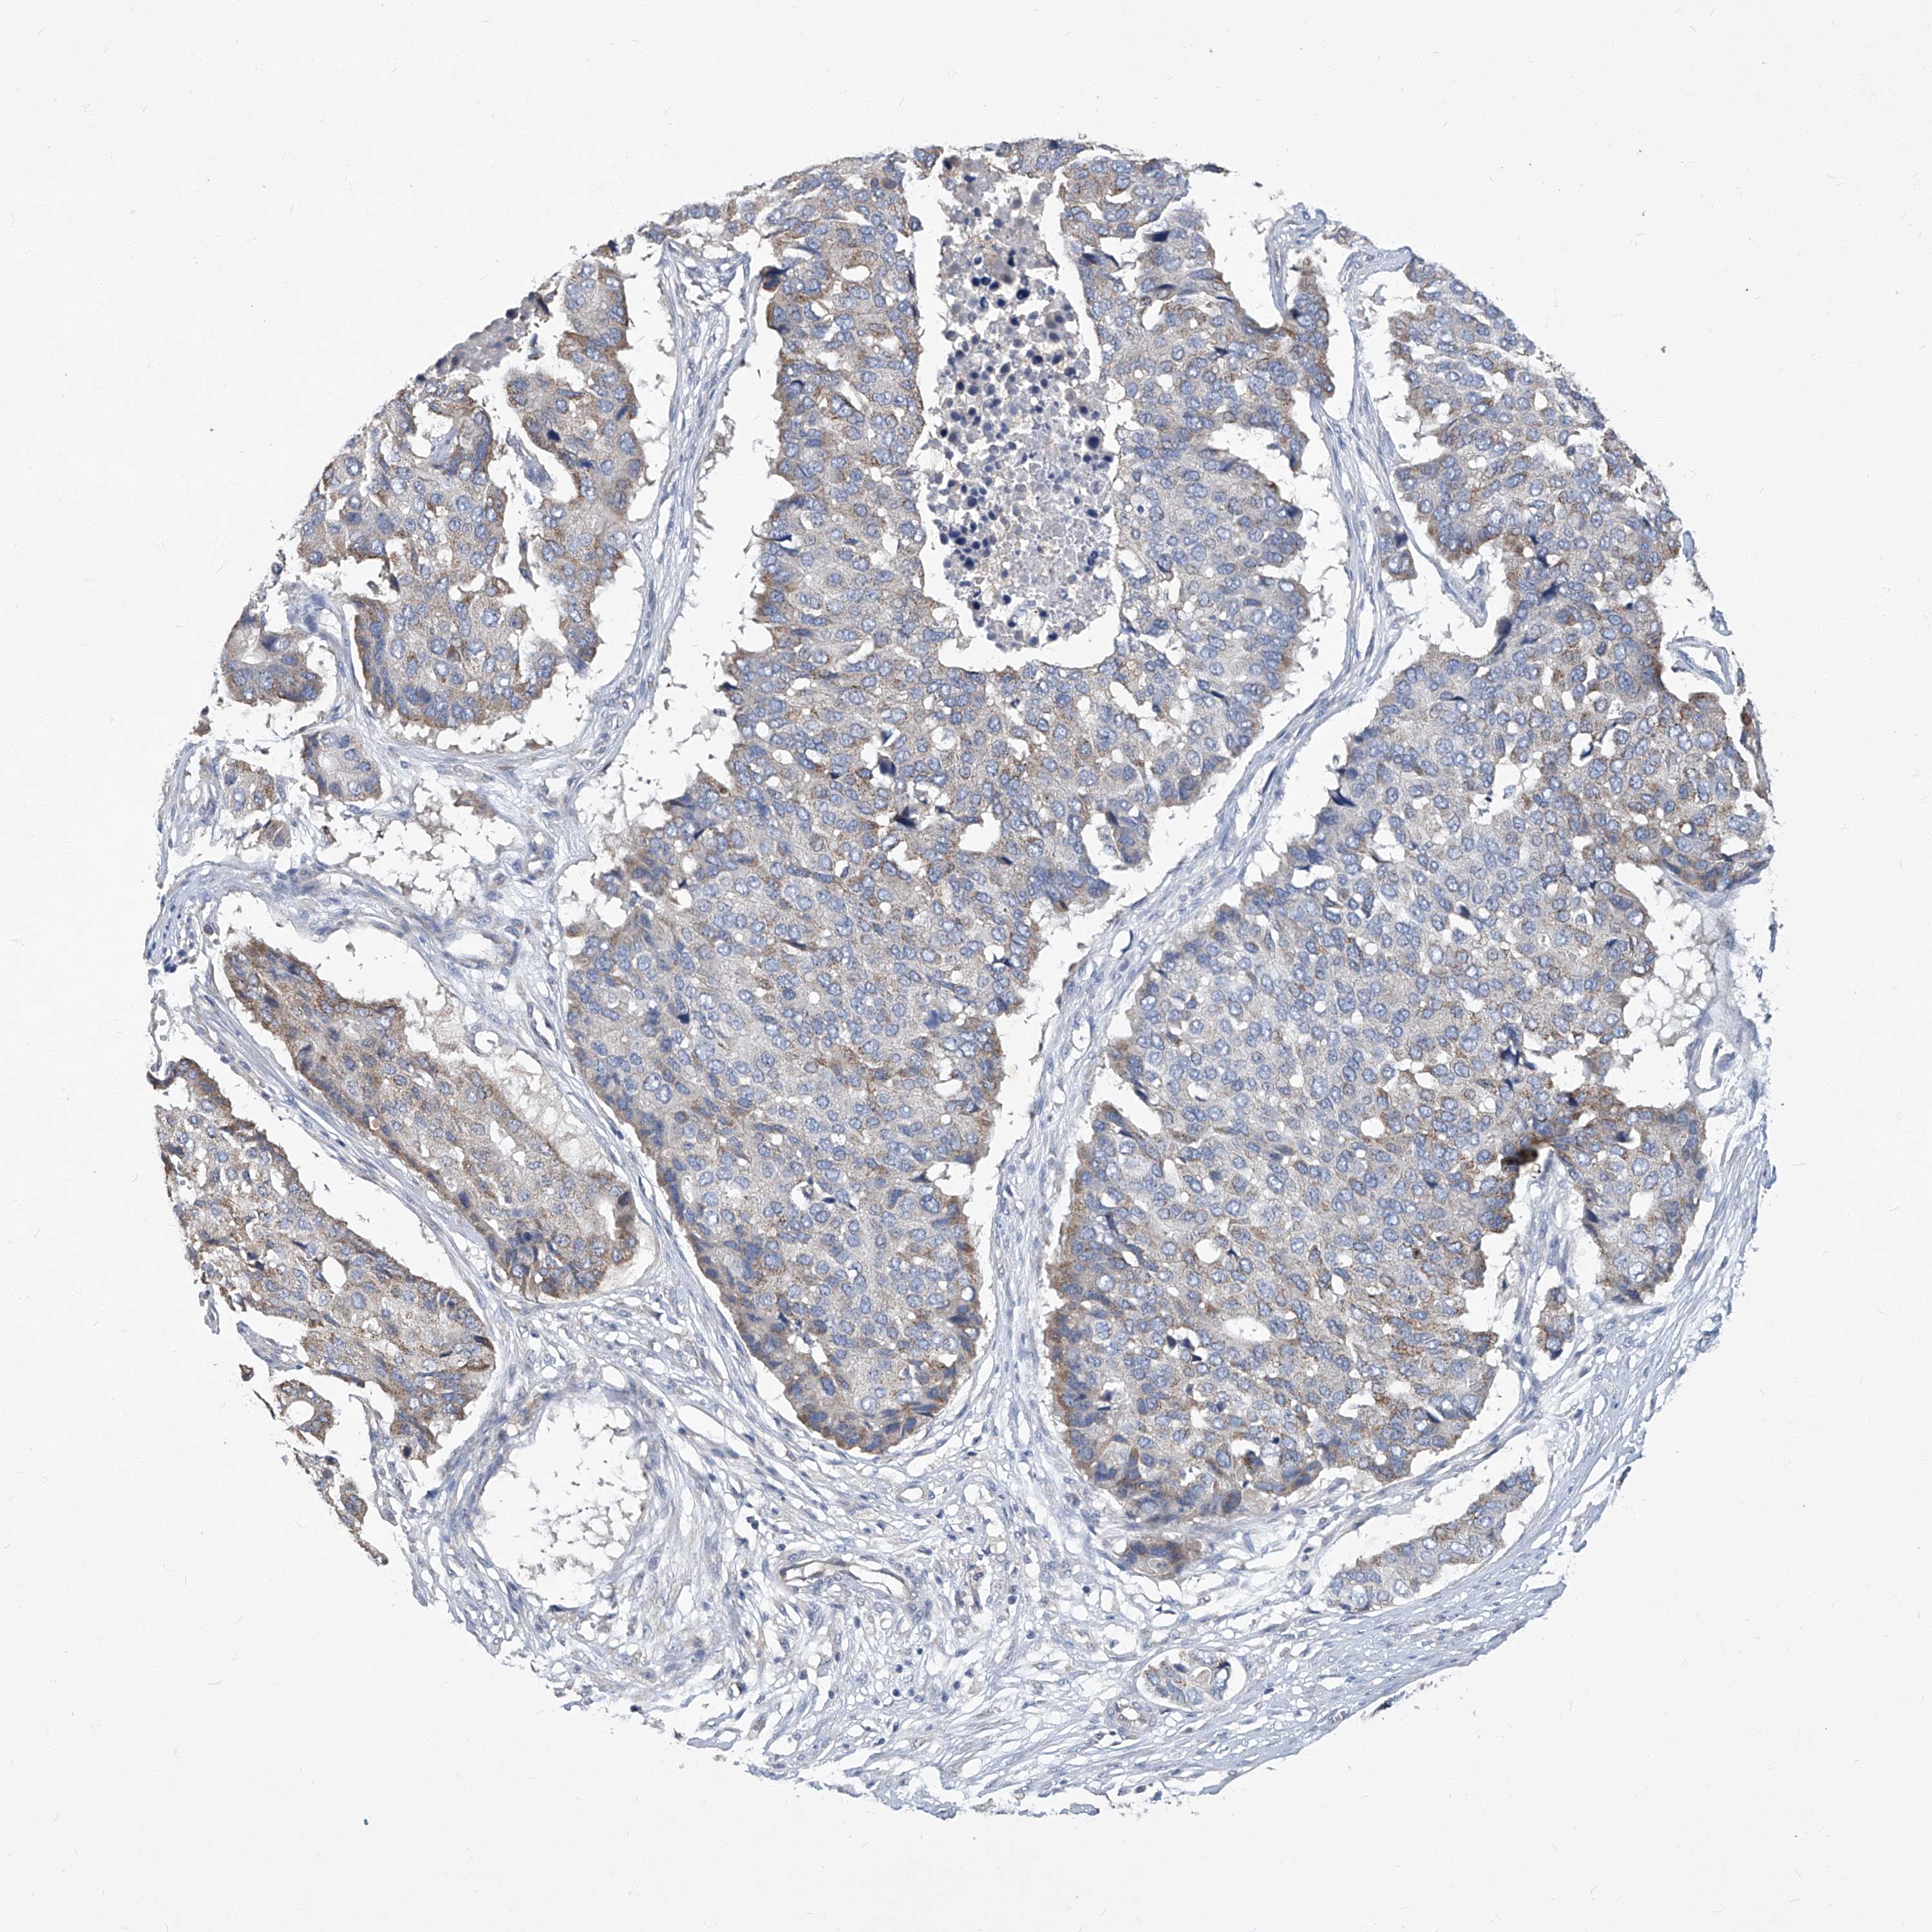

PANCREATIC CANCER - Protein expressioni

A mouse-over function shows sample information and annotation data. Click on an image to view it in a full screen mode. Samples can be filtered based on level of antibody staining by selecting one or several of the following categories: high, medium, low and not detected. The assay and annotation is described here.

Note that samples used for immunohistochemistry by the Human Protein Atlas do not correspond to samples in the TCGA dataset.

Antibody stainingi

Antibody staining in the annotated cell types in the current human tissue is reported as not detected, low, medium, or high, based on conventional immunohistochemistry profiling in selected tissues. This score is based on the combination of the staining intensity and fraction of stained cells.

Each image is clickable and will lead to virtual microscopy that enables deeper exploration of all samples and also displays staining intensity scores, fraction scores and subcellular localization as well as patient and tissue information for each sample.

Antibody CAB002441

Antibody CAB031481

Staining

High

Medium

Low

Not detected

Intensity

Strong

Moderate

Weak

Negative

Quantity

>75%

75%-25%

<25%

None

Location

Nuclear

Cytoplasmic/membranous

Cytoplasmic/membranous,nuclear

Adenocarcinoma, NOS

Adenocarcinoma, metastatic, NOS